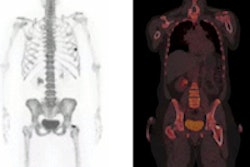

![]() |

| Transaxial F-18 NaF images from a 76-year-old woman include CT (A), PET (B), and fused PET/CT (C) images of the aortic arch. F-18 NaF uptake in atherosclerotic lesion coincided with calcification, as indicated by the arrows. Images courtesy of the Journal of Nuclear Medicine. |

For the remaining 223 lesions with F-18 NaF uptake (88%), researchers found radiotracer accumulation and calcification. However, the study stated, "only these 223 (12%) of the 1,930 total calcification sites showed prominent 18F-sodium fluoride uptake in at least some part of the calcified plaque."